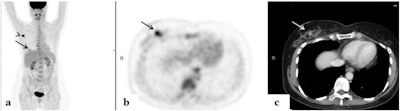

In addition, distant FDG-avid lesions were detected in 33 patients (10.2%). Seven patients without distant metastases had FDG-avid supraclavicular lymph node involvement and four had FDG-avid internal mammary lymph nodes.